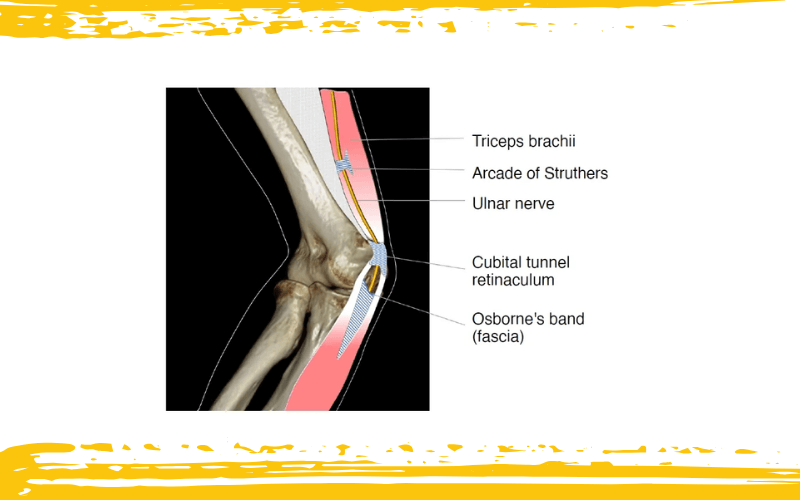

Aunque el nervio cubital puede comprimirse en varios puntos a lo largo de su trayecto por el codo, el túnel cubital se lleva el dudoso honor de ser el lugar más frecuente de atrapamiento. Pero no camina solo: desde proximal a distal, las zonas anatómicas vulnerables incluyen el septo intermuscular (donde se encuentra el arco de Struthers), la entrada del túnel cubital en el epicóndilo medial, el interior del túnel cubital propiamente dicho, y la región entre las dos cabezas del músculo flexor cubital del carpo, bajo la banda de Osborne.

Esquema que representa los sitios más frecuentes de atrapamiento del nervio cubital.

La banda de Osborne (fascia) se muestra como la fascia que cubre las cabezas humeral y cubital del músculo flexor cubital del carpo, tal como se describió originalmente. El retináculo del túnel cubital, que es distinto de la fascia de Osborne, constituye el techo del túnel cubital.